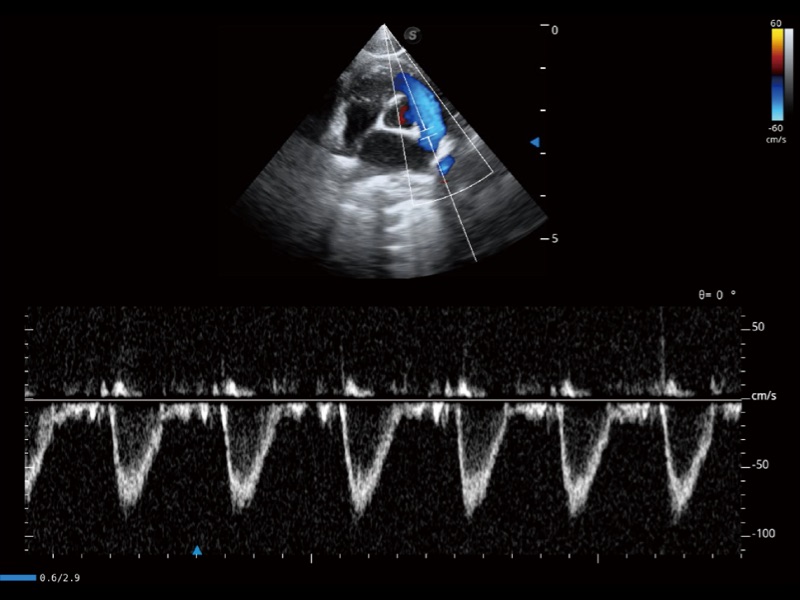

通过创新的 Matrix E自适应滤波器和超长时间域算法,极大提升超低速微细血流的检出能力,同时更精准地滤除软组织和噪声信号,为兽用医生提供以往无法通过常规血流获得的疾病诊断信息。

通过色彩血流和实时宽景相结合,可观察到完整的静脉或动脉的血流,方便医生检查。实时扫查过程中,如有任何操作失误也可以很容易地进行回扫擦除,而不会中断扫查。

采用红、橙、黄、绿、青、蓝、紫这七种肉眼最为敏感的色彩,直观地显示组织内血流灌注的时间先后信息,更精准捕捉血流灌注走行细节。